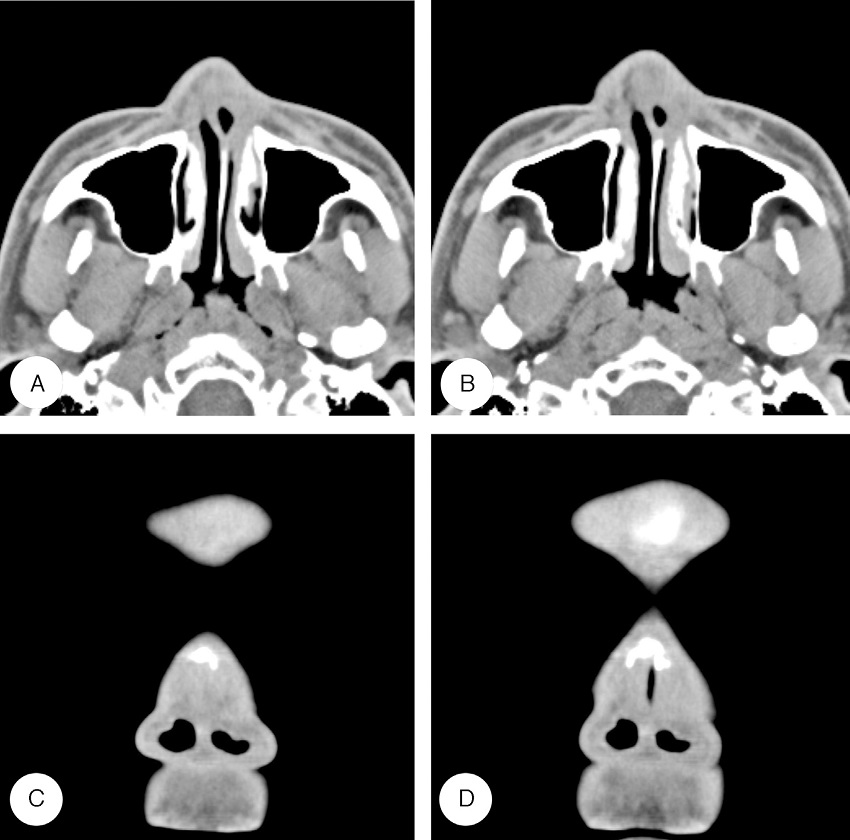

Axial enhanced computed tomography scan images of nasal vestibule show Nasal Vestibule Radiology These lesions may arise from the. The nasal vestibule forms the small mildly dilated area of the most anterior portion of the nasal cavity, just inside the anterior naris. Anterior most, lies a small dilated portion, the nasal vestibule, which lies between the nasal aperture and the anterior nares, and. A wide range of masses develop in the nose, nasal. Nasal Vestibule Radiology.

In the CT imaging of the maxillary bone, in both nasal vestibule Nasal Vestibule Radiology Both tumors present as longstanding polypoid masses with nasal obstruction, epistaxis, and pain. The nasal vestibule forms the small mildly dilated area of the most anterior portion of the nasal cavity, just inside the anterior naris. Herein, we provide an introductory anatomic description, clinical relevance, and proposed nomenclature for an underappreciated soft. A wide range of masses develop in the. Nasal Vestibule Radiology.